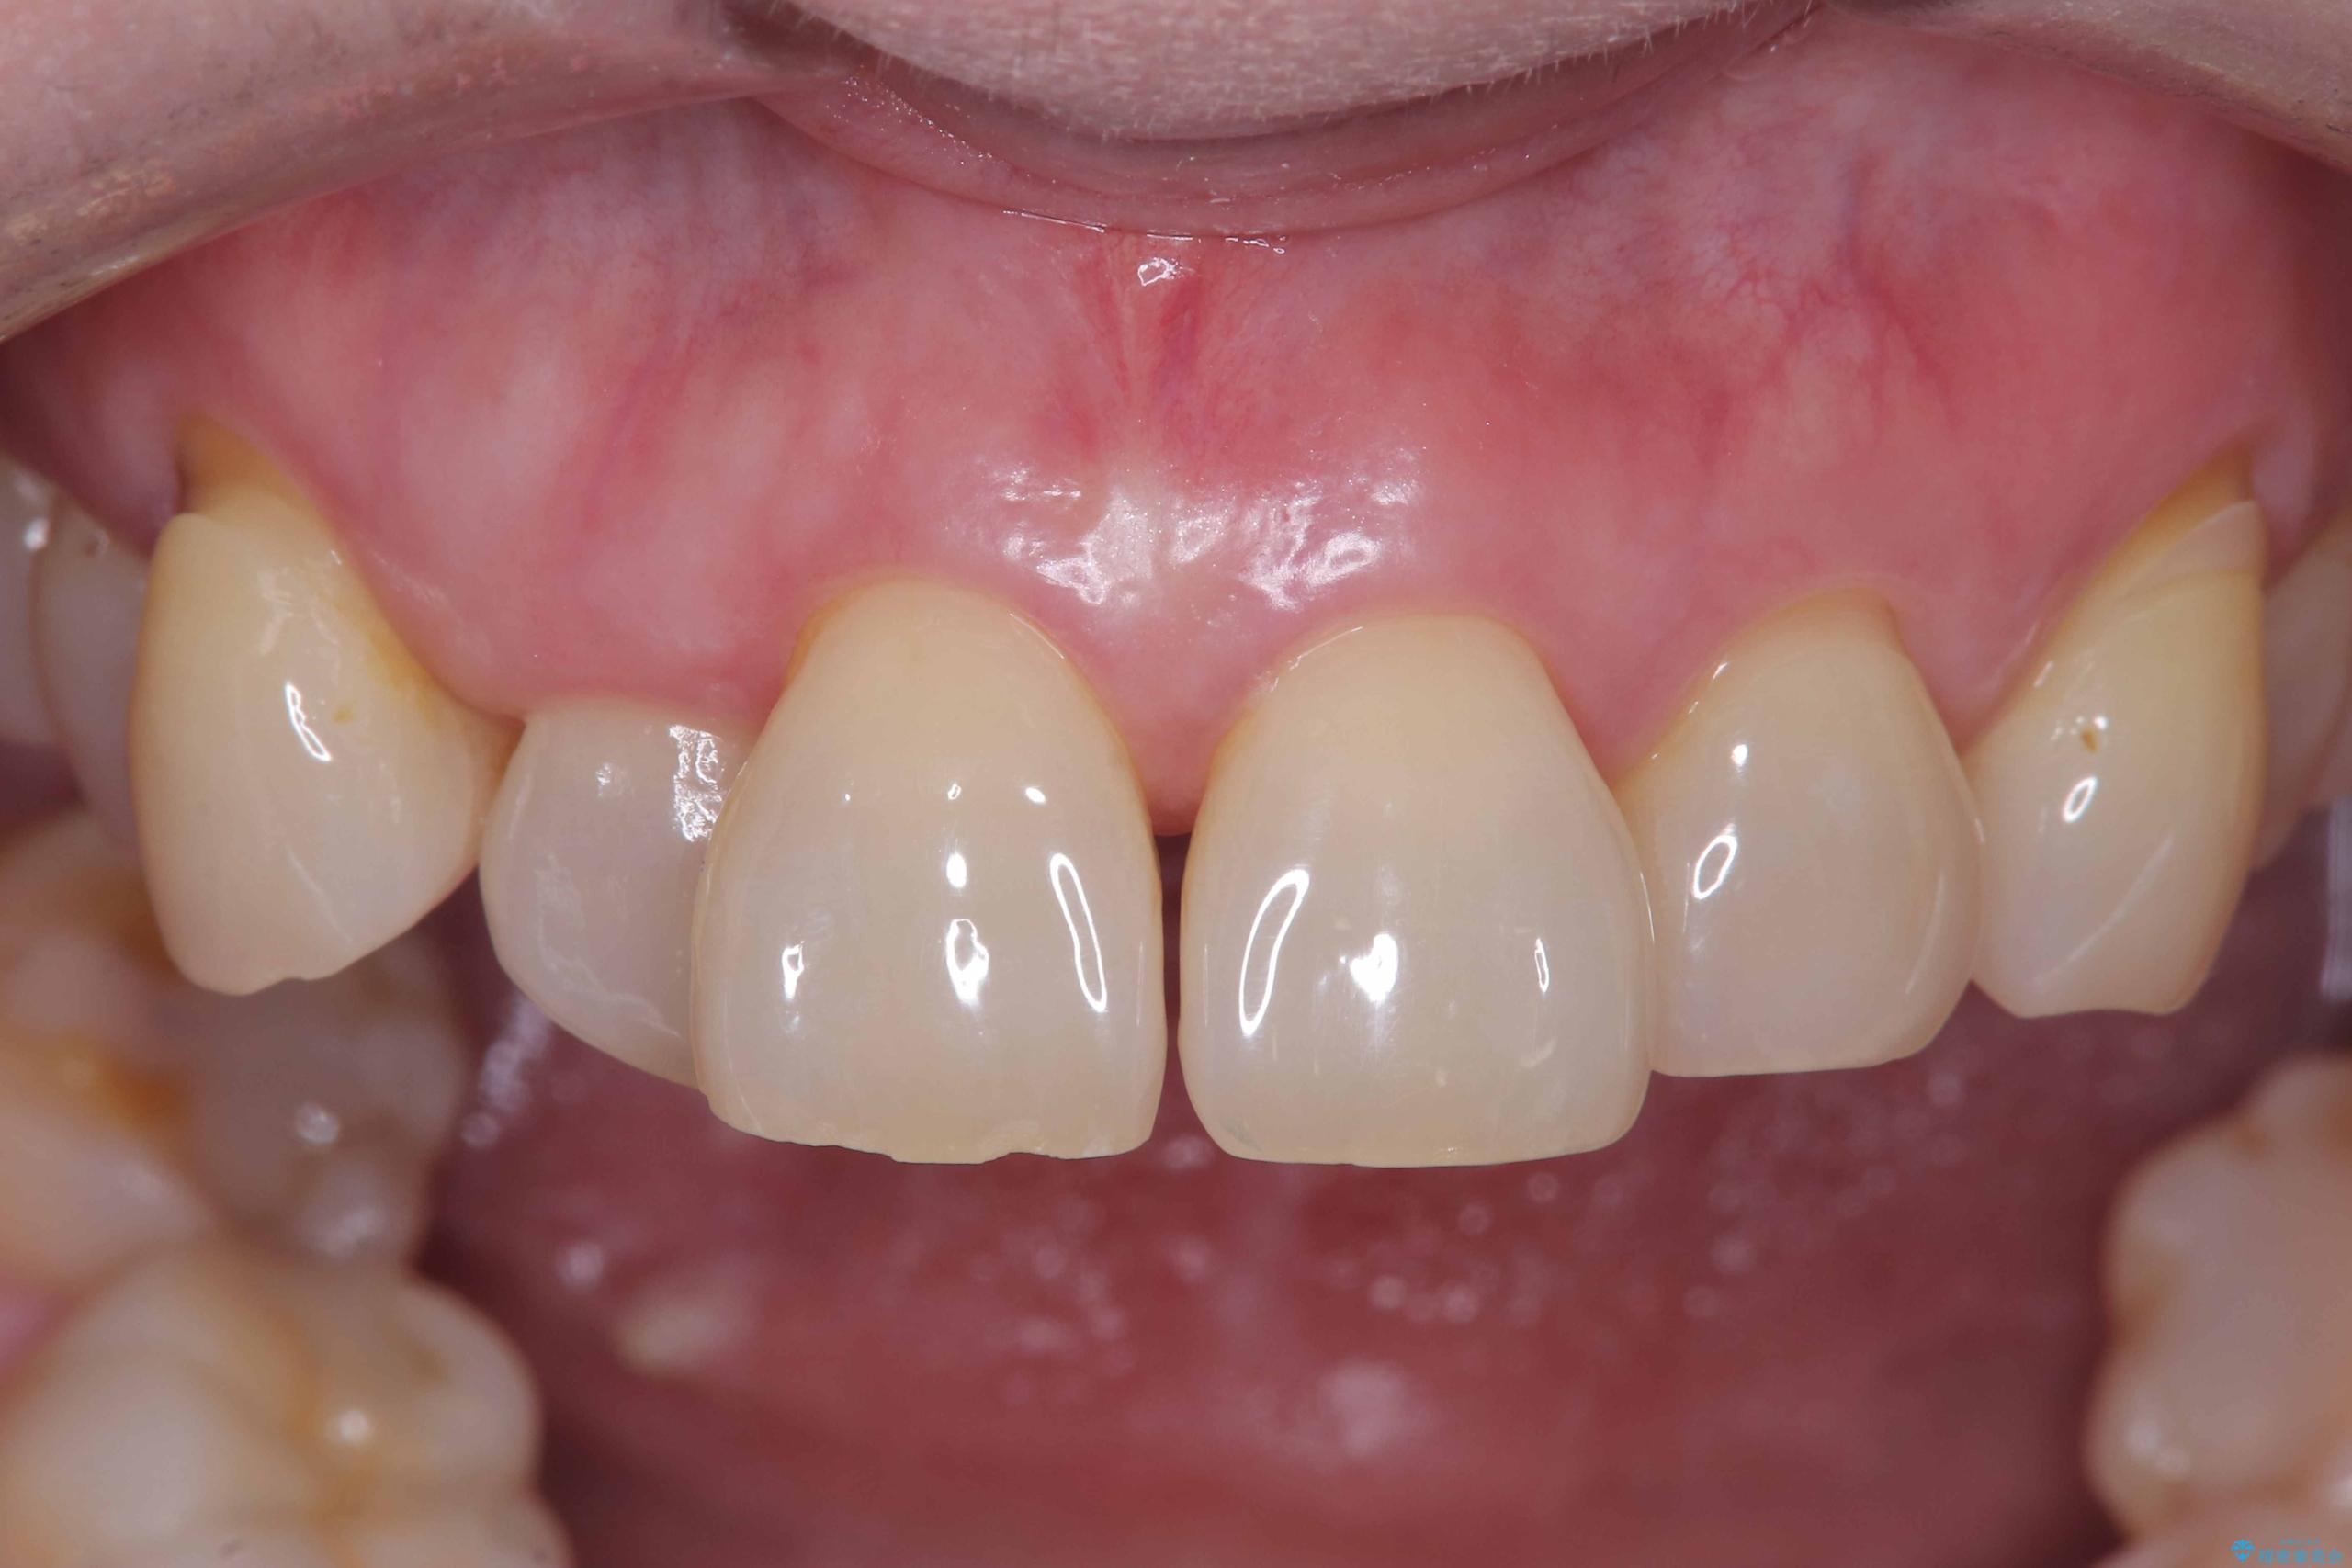

前歯の隙間とへこみが舌で触ると気になる|矯正治療は絶対にしたくない|抜歯即時インプラント+オールセラミッククラウンで審美修復

- 前歯の隙間とへこみが気になり、特に舌で触ると気になってストレスを感じるとのことで来院された患者様です。

そのため今回は、右上2番を抜歯し、右上1番および左上1番をオールセラミッククラウンで審美的に修復しました。